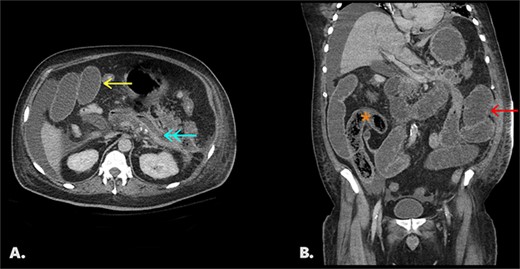

On initial CT imaging, avascular phlegmon and necrotic pancreatic tissue were observed in the expected retroperitoneal location of the pancreas (Fig. 1A).

(A) Initial non-contrast CT. Axial image shows extensive pancreatic necrosis and phlegmon (*). 1B/C Follow up CT with IV contrast (portal venous phase). Image 1B: axial image shows fluid replacement of tissue in the pancreatic bed (*). Image IC: coronal image shows fistula between pancreatic bed and duodenum (arrow) and bezoar in the distal duodenum (*).

On follow-up CT imaging, the pancreatic bed was fluid filled with tubular, avascular mottled material in the distal duodenum, representing pancreatic bezoar (Fig. 1B and1C).